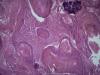

Опухоль матки |

Плоскоклеточный умереннодифференцированный рак,инвазия в железы.